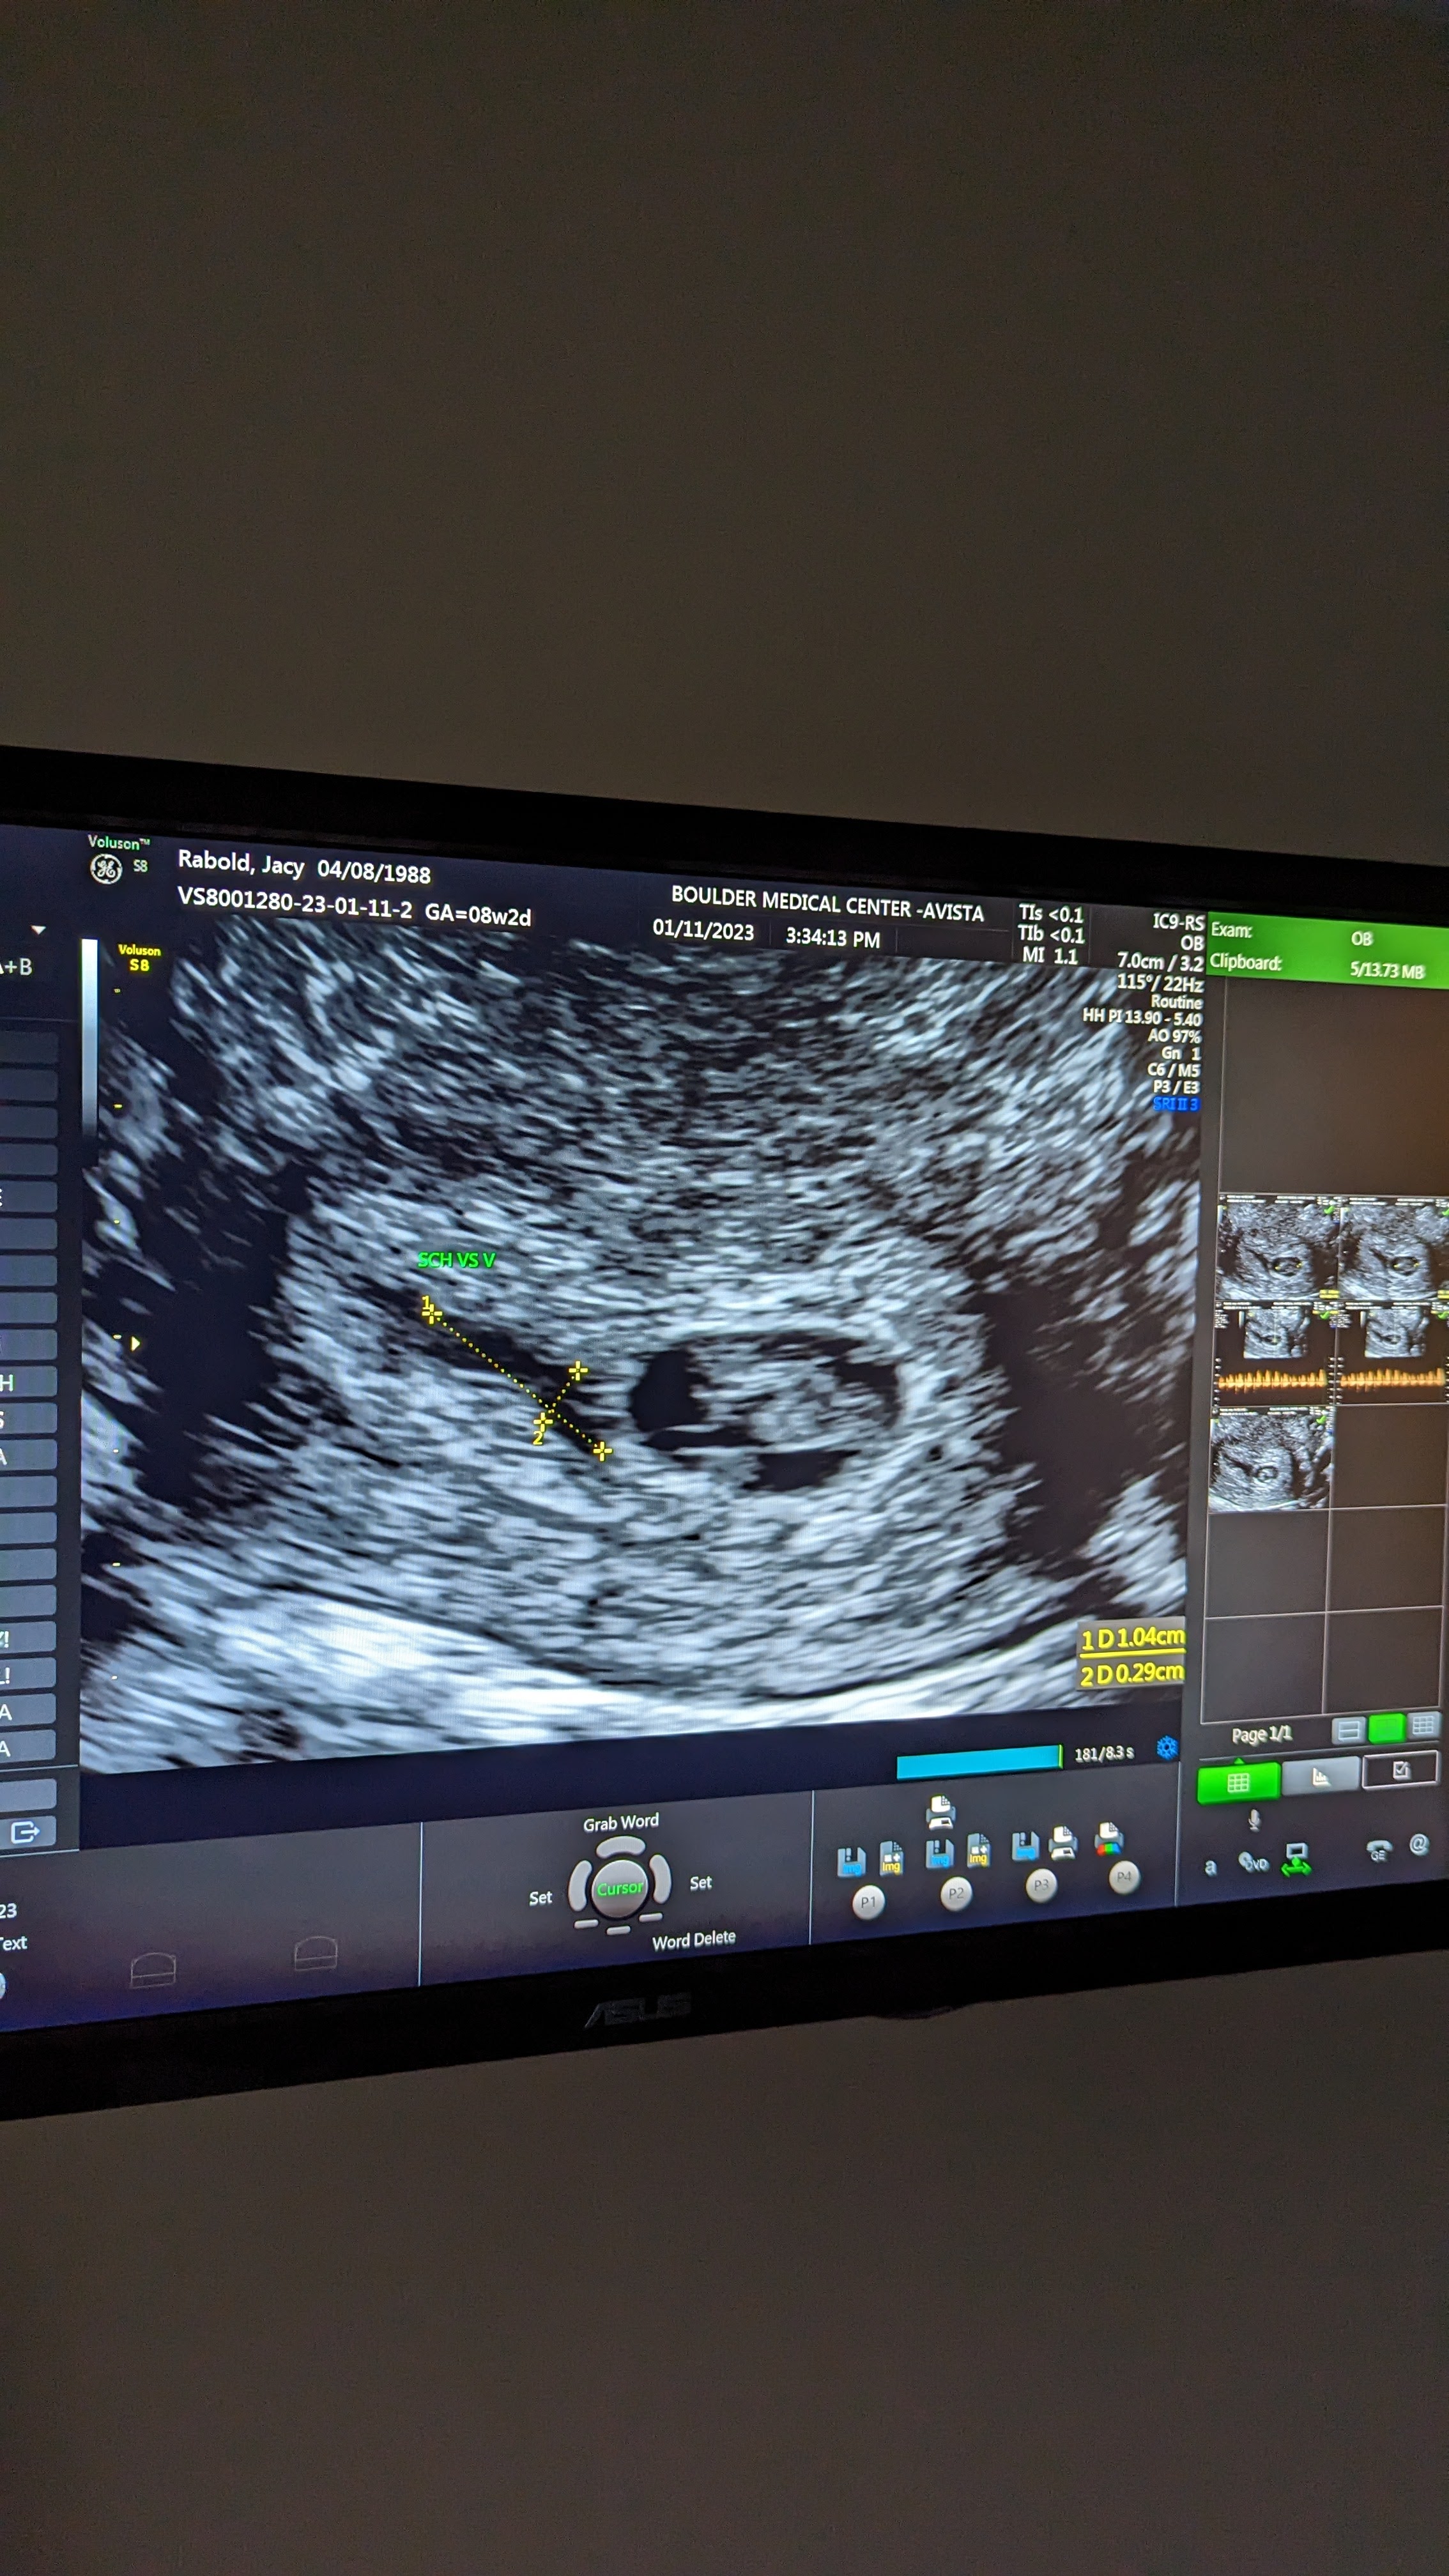

The holidays passed & January came and we got our official confirmation of pregnancy. A strong heart beat at 161 beats/minute. We left the appointment feeling hopeful.

On Tuesday night, I had some red flags that gave me enough of a pause to text my old Austin OB and see if she could get me first thing the next day. The next morning at the doctor it was immediately clear that the strong heartbeat I had seen a week prior was no longer so obvious. The doctor said she couldn’t see anything, but wanted to get the specialized ultrasound tech to confirm.

She confirmed what I already knew in my heart.

There was no heartbeat; I was experiencing a miscarriage.